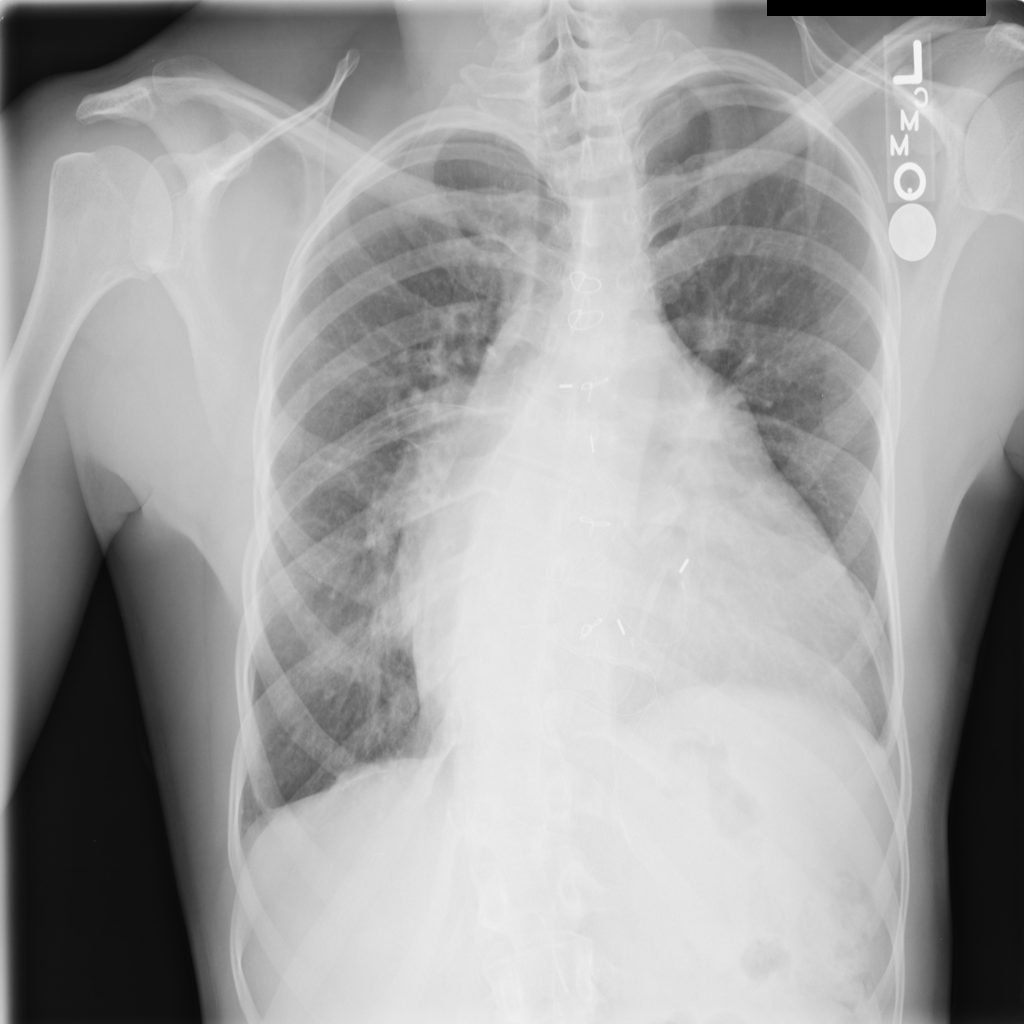

PAT-1BE4 · IMG-003Cardiomegaly

PAT-1BE4 · IMG-003

AP